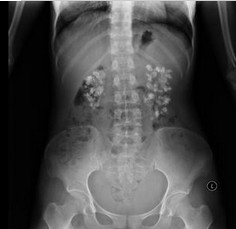

静脉尿路造影